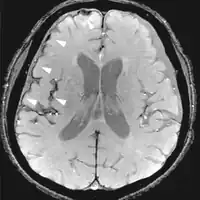

| Fluid-attenuated inversion recovery | FLAIR | Fluid suppression by setting an inversion time that nulls fluids | High signal in lacunar infarction, multiple sclerosis (MS) plaques, subarachnoid haemorrhage and meningitis (pictured).[76] |  | |